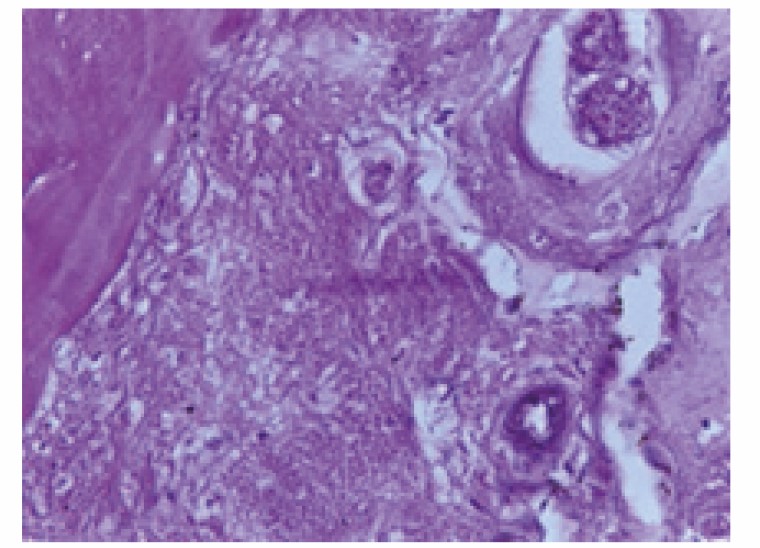

Гистологическое исследование костной ткани крыс I и II группы после лечения представлены на рисунках 1 и 2 (см. 2-ю стр. обложки). На фрагментах нижней челюсти животных, прослеживается положительная динамика восстановления костной ткани. Это проявляется в отсутствии остеокластов, уменьшении лакун, уплотнении и нормализации структуры ткани. Кроме того, наблюдается восстановление микроциркуляторного русла, формирование сосудов и грануляционной ткани.

Рисунок 2. Структура костной ткани фрагмента нижней челюсти крысы после иммунотропной композиции с витамином D3

Примечание. Окраска гематоксилином и эозином, увеличение в 400 раз.

Figure 2. Structure of the bone tissue of a fragment of the lower jaw of a rat after an immunotropic composition with vitamin D3

Note. Hematoxylin and eosin staining, 400× magnification.